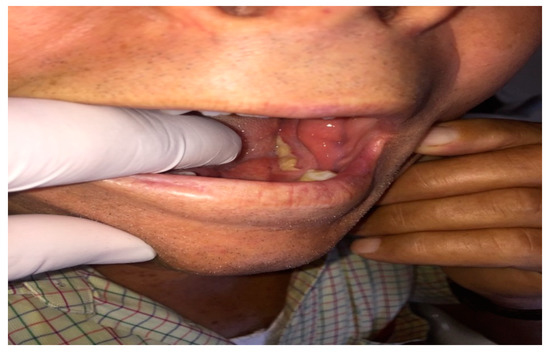

| SubGroup B1 Neoplasm 1st visit | 12 contacts | Skin Carcinoma: 3 | Skin Biopsy: 2 |

| Mucosa Oral Carcinoma: 8 | Oral Biopsy: 4 | ||

| Submandibular gland Carcinoma: 1 | |||